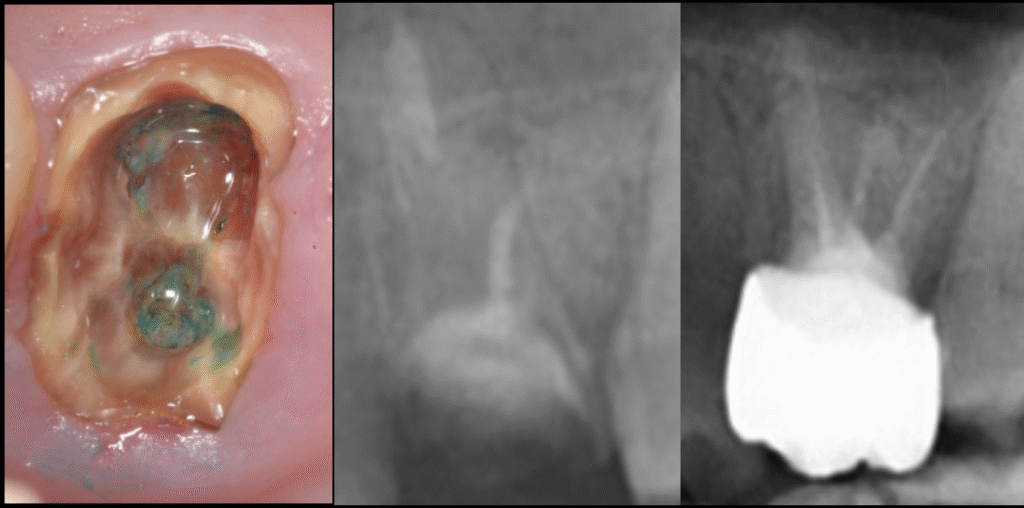

初診時の状態は以下の通りでした。

- 広範囲の二次カリエスで残根状態

- 咬合面の高さが低く保持力が不足

- レントゲンに亀裂を疑う像

- 歯肉の発赤・腫脹

- 何度も被せ物が脱離している既往

- 噛むと痛む

①精密根管治療—マイクロスコープ下で感染源を徹底除去

まずラバーダム防湿を行い、マイクロスコープ(歯科用顕微鏡)を使用し、

- 残根内部の感染除去

- 亀裂の有無の確認

- 根管形態の正確な把握

- 歯質強度の評価を行いました。

最も重要なのは、

破折(歯根破折)なのか、深い虫歯なのかを見極めること。

拡大視野で慎重に精査した結果、

・致命的な破折はなし

・歯質は薄いが補強可能

・根尖部の感染はコントロールできる

という結論に至りました。